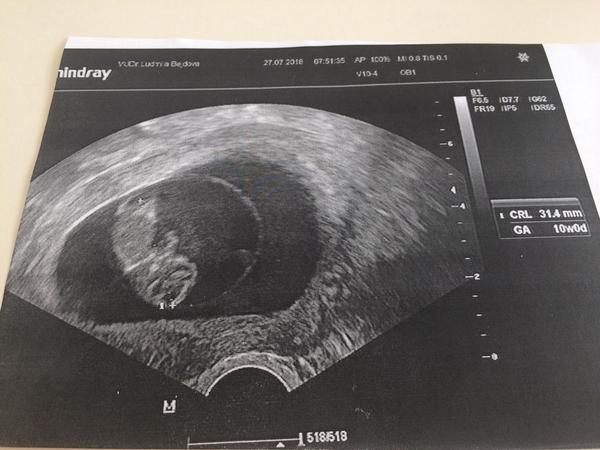

Tak jsem doma. Nakonec jsem skoncila s ANTB Protoze mam v cevkovane moci bílé krvinky celkem dost pry. Takze nejspis silný zanet. Od ceho to muze byt mi nerekl Protoze Ja jen polehavam doma. Takze ač nerad tak musel nasadit šetrné antibiotika. A Ja mam stale pochybnosti s tim je vubec brat. Nemáte rady jak to obejít ??? Jinak na UTZ vse v poradku. Dokonce jsme povyrostli o 2,5cm za 10dni. A TP se nam změnilo na Valentýna.